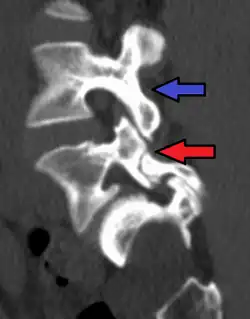

Anterolisthesis L5/S1 -

Anterolisthesis L5/S1. Blue arrow normal pars interarticularis. Red arrow is a break in pars interarticularis. -

Anterolisthesis L5/S1